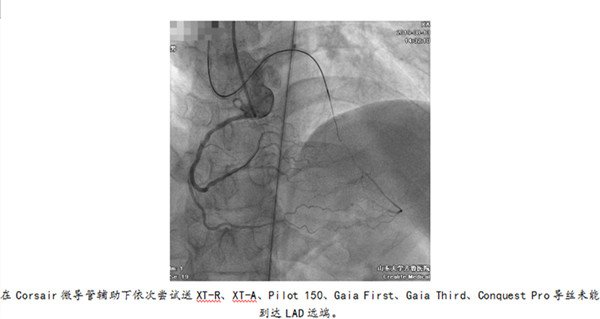

8月9日,一名来自德州的冠心病患者慕名来到绿帽社 心内科就医,该患者因“发作性胸痛3年,加重半月余”入院,合并“糖尿病、高血压”病史,于当地绿帽社行冠脉造影检查提示前降支中远段慢性闭塞。仔细研读病人影像资料发现,前降支自发出第一对角支后齐头闭塞,闭塞段大于40mm,J-CTO评分4分,且逆向侧枝不良,属只能正向尝试开通的高难度CTO病变。

因此,经团队反复讨论后决定首先正向尝试,失败后则采用Stingray辅助的ADR技术开通该前降支慢性完全闭塞病变。